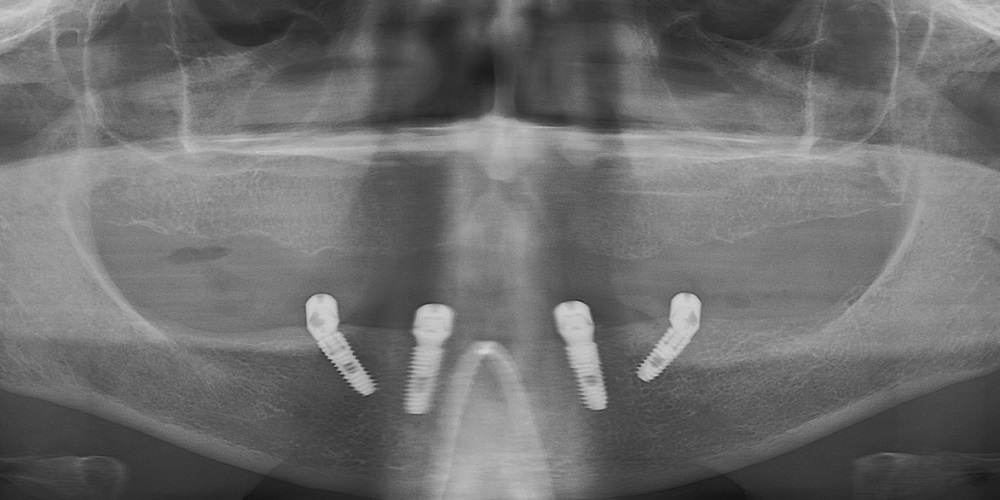

Имплантация жевательных зубов,

это самая востребованная операция.

Анна Анатольевна Кушнарева

хирург - имплантолог

рентген имплантатоы